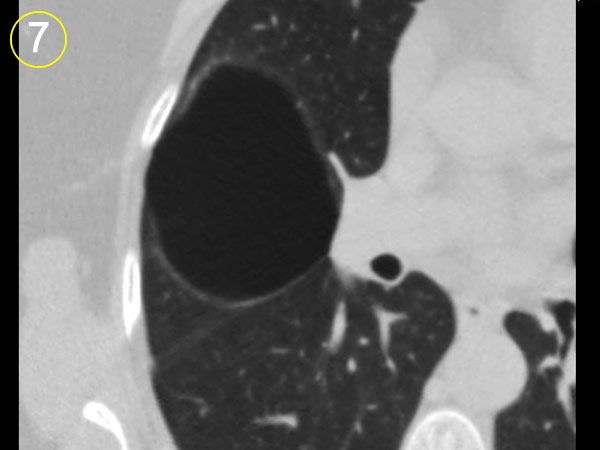

La tomografía

computarizada del tórax

y su adecuada interpretación es de gran ayuda diagnóstica

en las patologias del tórax.